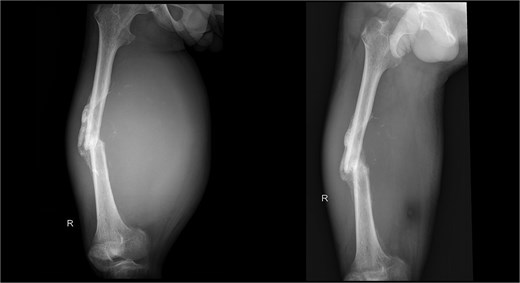

X-ray imaging post operation of the right femur reveals a mid-shaft fracture with prominent callus formation.